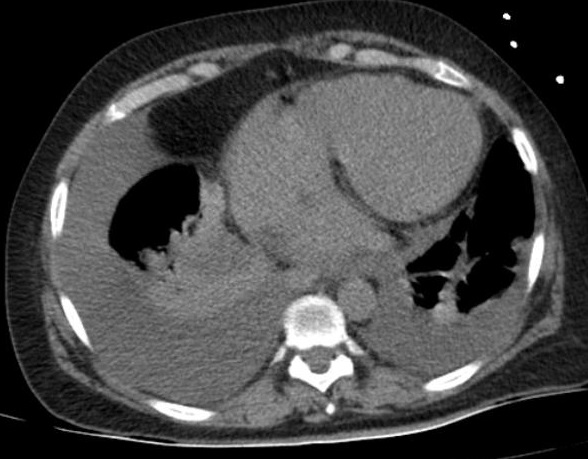

Image radiologique TDM d'une pleuresie du

poumon droit de moyen abondance . La liquide

transudat ou exsudative declive au sinus costo

diaphragmatique lateral et posterieur du poumon

droit en formant de aspect de masse non systematisee

, isopdensite , homogene . Image radiologique

TDM en coupe axiale et coronal , fenetre

mediastinale et image radiologique TDM coronal ,

fenetre parenchymateuse |